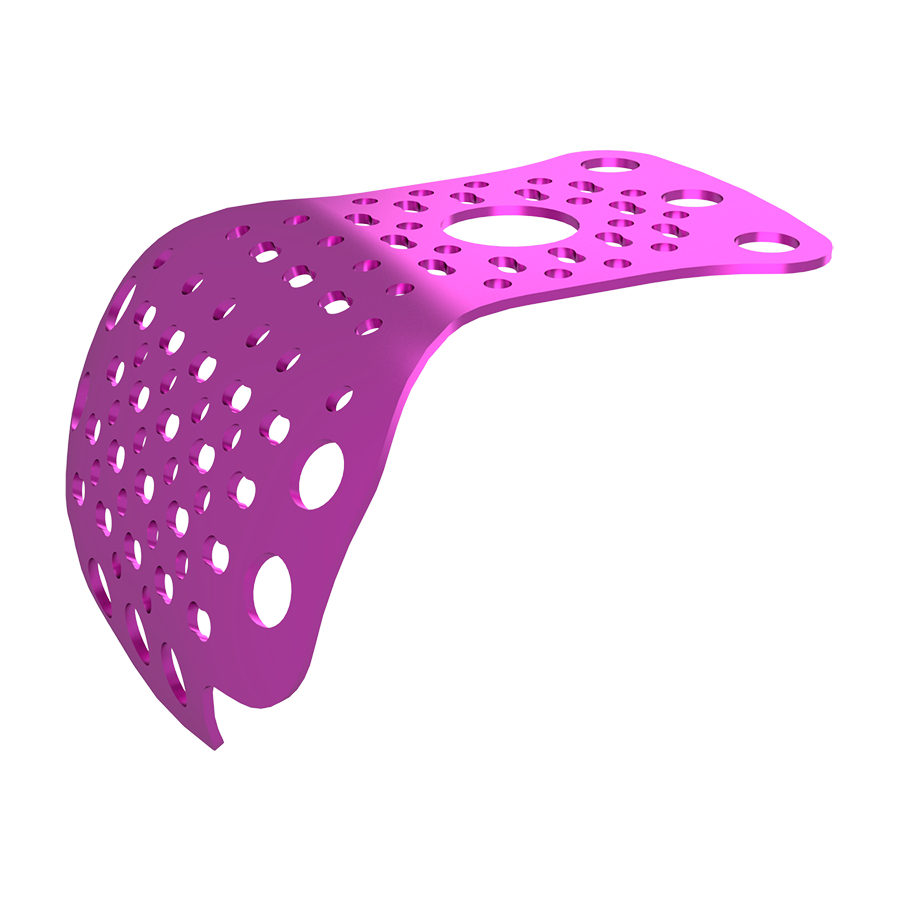

Our Titanium Mesh Membrane is designed to offer optimal support in guided bone regeneration (GBR) procedures, combining structural stability with excellent adaptability. The ultra-thin, anatomically contoured design allows for a comfortable fit and easy surgical handling, while maintaining strong support for the defect area. It can be easily trimmed and shaped to match various bone contours, making it a reliable and versatile choice in both simple and complex cases.

Key Features:

Easy to cut and shape: Allows for fast, precise contouring during surgery

Enhanced fixation: Designed to be used with bone tacks for stable placement

Ultra-thin design: Reduces foreign body sensation while ensuring structural strength

Anatomical curvature: Provides high intraoperative fit and reduces surgical time

Perforated (lightening) holes: Ensure good vascularization and promote blood supply to the regeneration site